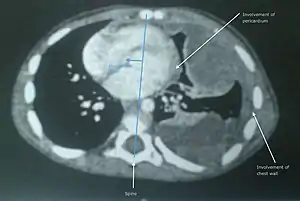

Undifferentiated soft tissue sarcoma in left lung of young child